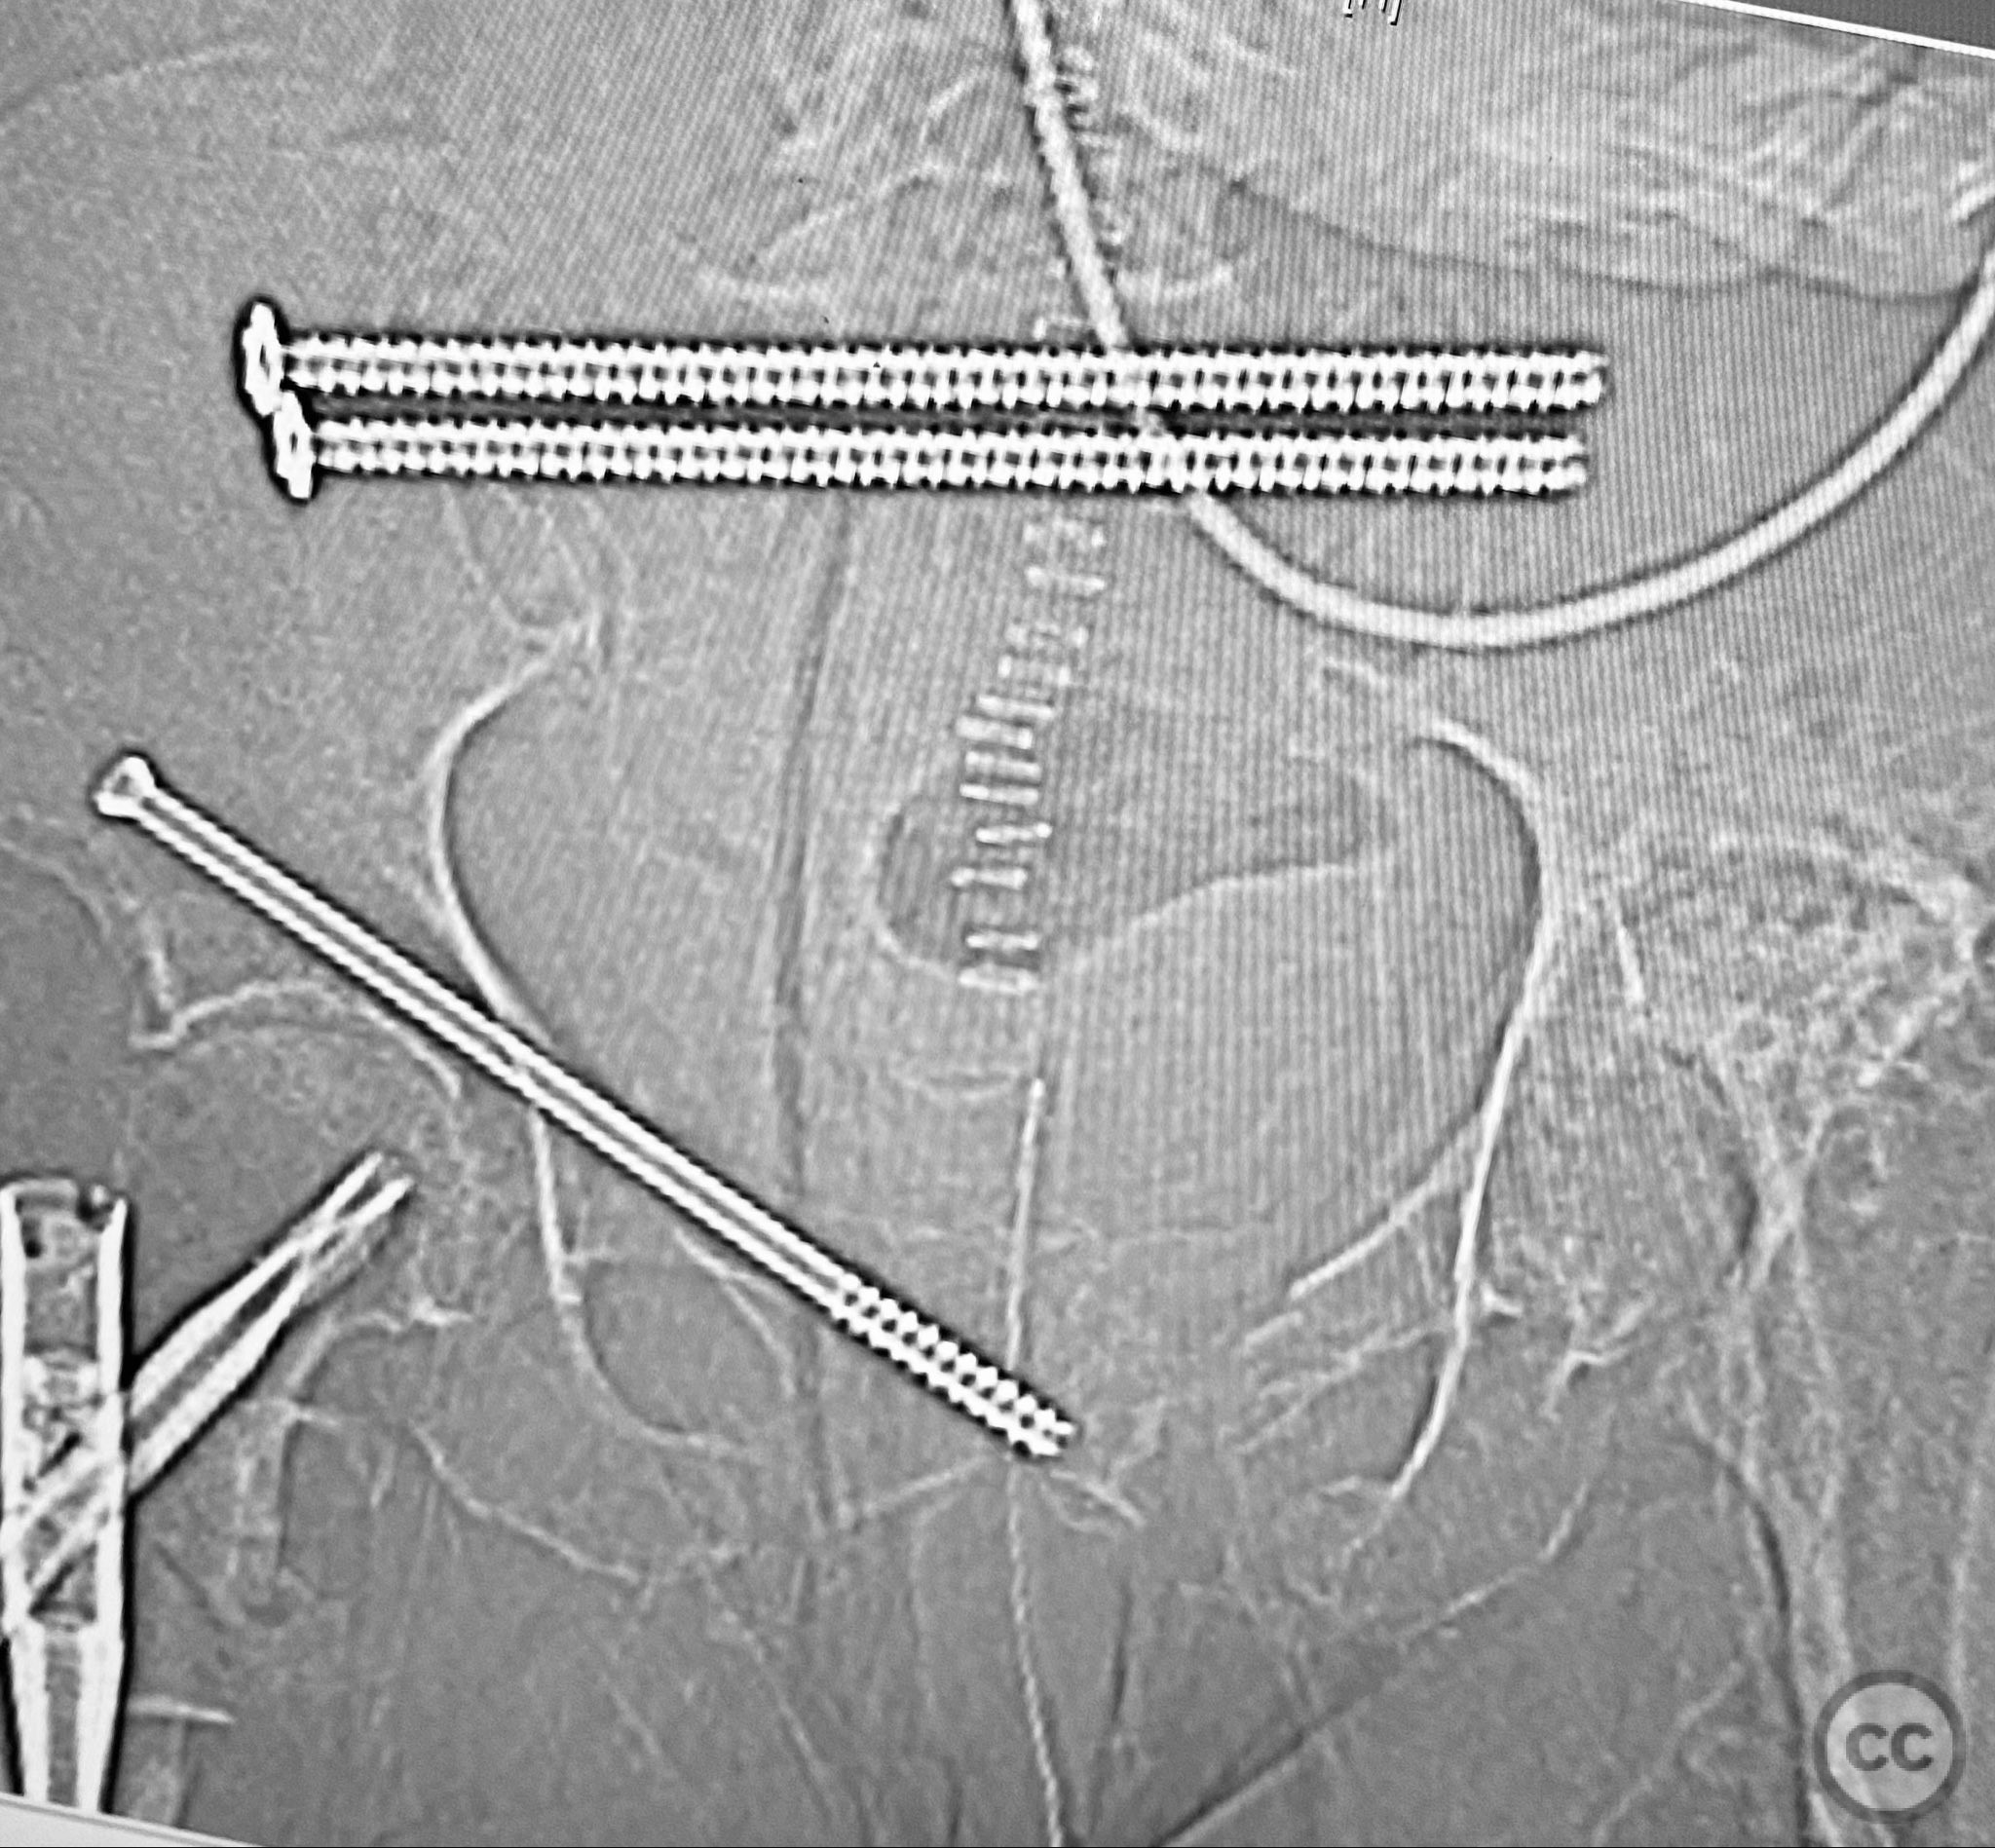

Planning remarks:  The preoperative plan included early closed reduction maneuvers under fluoroscopic guidance, percutaneous stabilization of the pelvic ring with cannulated screws, and intramedullary nailing of the proximal femur. The anatomical approach for pelvic fixation was percutaneous iliosacral screw placement; for the femur, a standard antegrade intramedullary nailing technique was planned.

Anatomical surgical approach:  Percutaneous iliosacral screw fixation was performed through small lateral gluteal incisions, with blunt dissection to the outer table of the os ilium. Under fluoroscopic guidance, guidewires were advanced across the sacroiliac joint into the S1 body, followed by cannulated screw insertion. For the proximal femur, a longitudinal incision was made proximal to the greater trochanter, splitting the fascia lata and gluteus medius fibers to access the piriformis fossa. A guidewire was inserted into the medullary canal, followed by sequential reaming and insertion of an intramedullary nail.

Orthopaedic implants used:   Cannulated iliosacral screws, antegrade intramedullary femoral nail